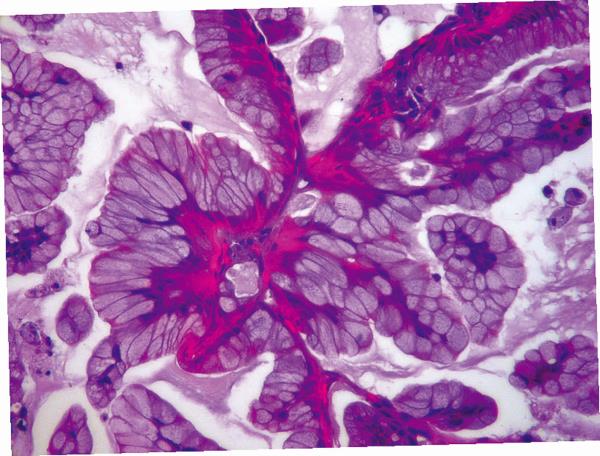

Слизистая аденокарцинома легкого под большим увеличением – слизь заполняет светло-розовые вакуоли в клетках, а также клубится вокруг в виде розовых облаков.